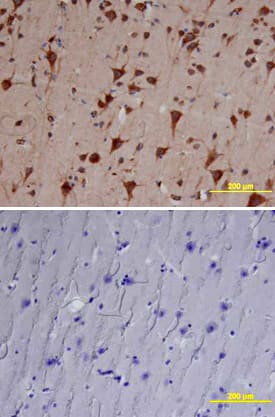

Cathepsin B antibody in Human Brain by Immunohistochemistry (IHC-P).

Cathepsin B in Human Brain.

Cathepsin B was detected in immersion fixed paraffin-embedded sections of human brain (cortex) using Goat Anti-Human Cathepsin B Antigen Affinity-purified Polyclonal Antibody (Catalog # AF953) at 10 µg/mL overnight at 4 °C. Tissue was stained using the Anti-Goat HRP-DAB Cell & Tissue Staining Kit (brown; CTS008) and counterstained with hematoxylin (blue). Lower panel shows a lack of labeling if primary antibodies are omitted and tissue is stained only with secondary antibody followed by incubation with detection reagents. View our protocol for Chromogenic IHC Staining of Paraffin-embedded Tissue Sections.